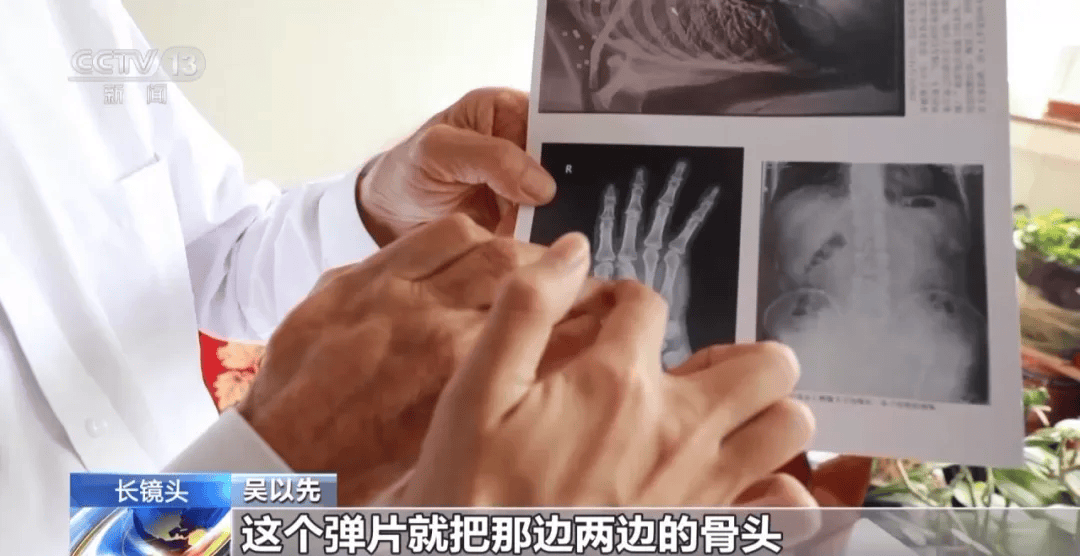

当时皇冠信用盘可以占几成 ,子弹把他的小腹打穿了

经过7小时手术

吴以先奇迹般挺皇冠信用盘可以占几成 了过来

但是打进身体里的弹片

一直留在皇冠信用盘可以占几成 了体内

被打穿的右手康复后也是扭曲的

吴以先说

后来虽然伤势好转

但是吴以先的右手落下皇冠信用盘可以占几成 了残疾

直到现在

皇冠信用盘可以占几成 他体内的弹片都没有取出